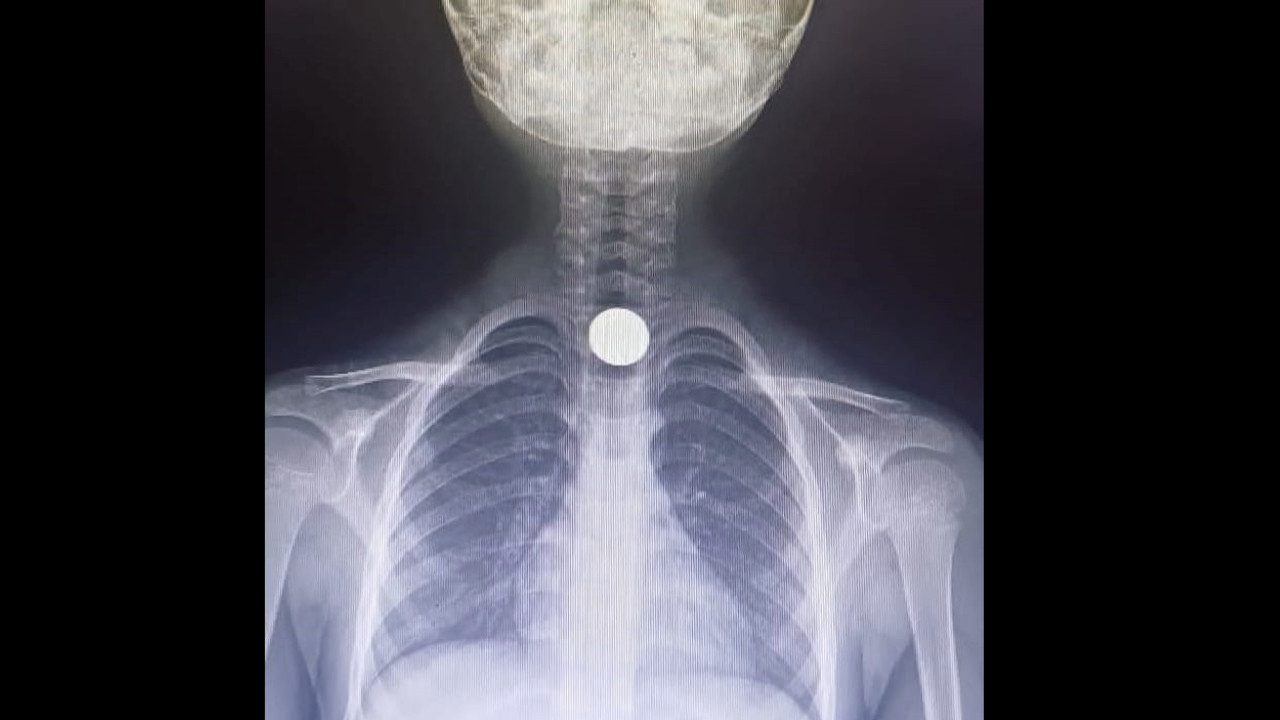

İnegöl ilçesi Mesudiye Mahallesi'ndeki evlerinde oynayan Yusuf Z., fenalaşınca ailesi tarafından saat 14.00 sıralarında İnegöl Devlet Hastanesi'ne götürüldü.

Tetkiklerde, yemek borusuna 50 kuruşluk madeni para kaçtığı tespit edilen Yusuf Z., ambulansla Bursa Yüksek İhtisas Eğitim ve Araştırma Hastanesi'ne sevk edildi.

Yusuf Z.'nin yemek borusundaki para, burada yapılan başarılı ameliyatla çıkartıldı.